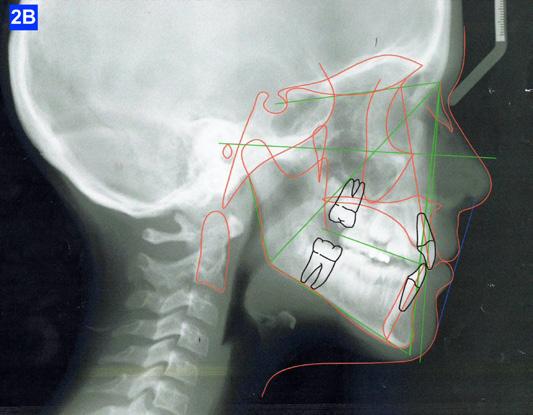

Lateral Cephalometric radiogram revealed a narrow airway in the tonsil area (5.0 mm), retrognathic maxilla and mandible (SNA - 78°, SNB - 76°), retrusive maxillary incisors (U1/SN - 91°), retrusive mandibular incisors (L1/GoM - 83°). She was Class III skeletally as ANB, Wits and the Harvold ∆ were – 2.4°, -5.0 mm and 24.8 mm The patient was hyper-divergent as seen from NS/GoM of40° and a Lower gonial angle of 79.7°. The patient was in CVMS 2 - 3 (Cervical Vertebrae Maturation Stage) (Figure 2-B) and an A-P Radiogram revealed a posterior crossbite (Figure 2-C).

Figure 2A: Pre-treatment, Panoramic radiogram Figure 2B: Pre-treatment, lateral Cephalometric radiogram